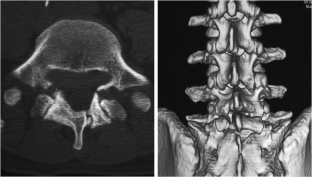

Atypical, unusual, and misleading imaging presentations of spondylolysis

Although lumbar spondylolysis is a widely known and easily recognizable condition in its typical presentation, there are some less well-known forms that may occasionally be challenging and/or demand special attention on imaging. Examples include: acute and/or incomplete lesions; unilateral defects; lesions at unusual levels (cervical, upper lumbar, and multi-level spondylolyses); iatrogenic lesions; non-isthmic spondylolysis; and spondylolysis related to underlying diseases. In addition to their atypical, uncommon or confusing imaging presentations, these forms of spondylolysis are far rarer than the classic type and have been described, to a great extent, in the surgical literature, thus reducing the awareness of radiologists about them and raising the potential for misdiagnosis and inadequate treatment. In this review the authors address these special manifestations of spondylolysis, stressing the more important features to be considered in the differential diagnosis and the impact of a precise diagnosis of spondylolysis on the patient’s care.